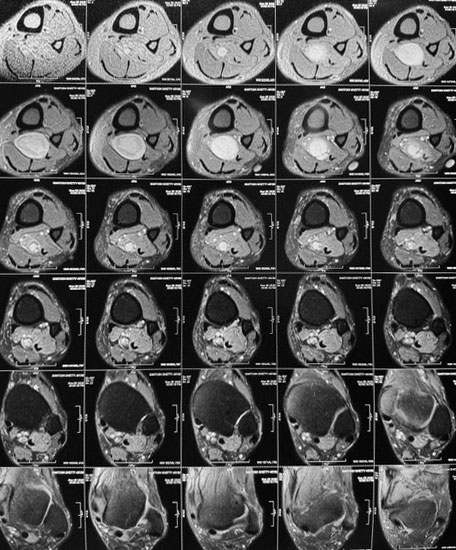

Surgical Highlights